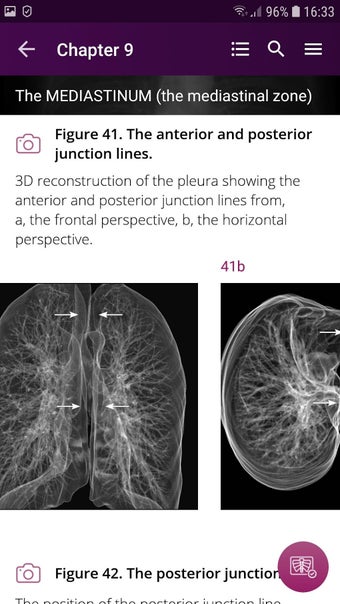

Radioloji'yi Keşfet: Göğüs Röntgeni Yorumlama, göğüs röntgeninin yorumlanmasının anlaşılmasını artırmak için tasarlanmış bir eğitim uygulamasıdır ve doktorlar, tıp öğrencileri ve radyologlar tarafından kullanılması amaçlanmaktadır. Uygulama, en küçük detayları görüntülemek için yakınlaştırılabilecek yüksek kaliteli görüntüler ve her bulgunun önemini anlamanıza yardımcı olacak bir sesli yorum içerir.

Uygulamanın amacı, kullanıcıların farklı x-ışını bulgularını ve bunların bir hastalığın teşhisinde nasıl kullanılabileceğini daha iyi anlamalarına yardımcı olmaktır. Uygulama, göğüs röntgeni yorumlaması için gerekli çeşitli yapı taşlarını kapsayan 5 bölüme ayrılmıştır.